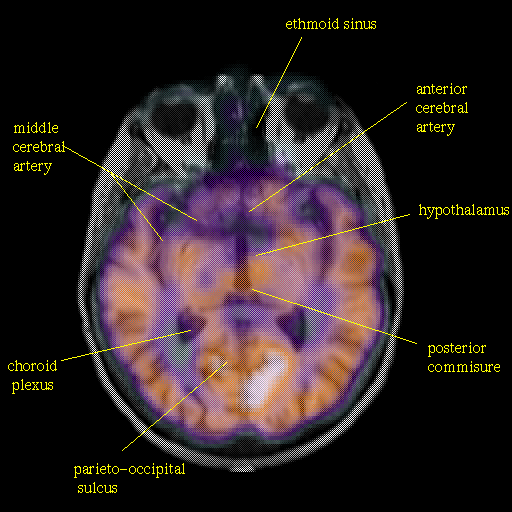

overlay: Slice 25

Slice 25

Pointers

Labeled